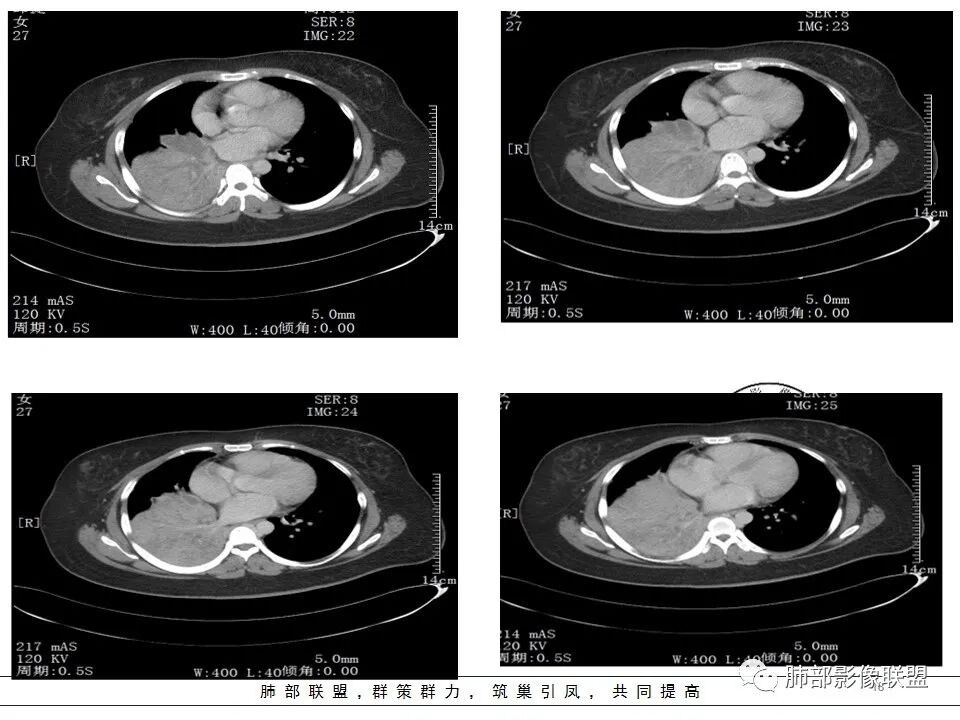

女,27岁,右肺下叶支气管闭塞,圆形软组织肿块和不张肺,增强不均匀强化,见片状坏死,多个纵隔淋巴结肿大,无钙化空洞及卫星灶;考虑恶性占位,肺肉瘤或鳞癌合并肺不张,鉴别诊断:结核,肺脓肿

右肺下叶支气管闭塞,圆形软组织肿块和不张肺,增强不均匀强化,见片状坏死,多个纵隔淋巴结肿大,无钙化空洞及卫星灶。鳞癌?肺脓肿?

发热咳嗽,右肺下叶可见团块状实变密度影,局部膨隆,并可见胸膜牵拉,相应下叶支气管未见显示,增强后肿块近端呈不均匀强化,可见大片状坏死,内血管略变细,毛糙,周围肺组织支气管内可见粘液栓形成,另纵膈肿大淋巴结,考虑恶性肿瘤,鳞癌,伴阻塞性肺不张,淋巴结转移

CT扫描示右肺下叶支气管堵塞,类圆形大肿块伴胸膜下大片肺实变影,增强扫描类圆形肿块延迟强化,见少量坏死,余实变区增强可见内部血管走行。纵隔见肿大淋巴结。考虑为恶性病变伴右肺下叶肺不张

右下肺大片实变影,近肺门处明显膨隆,远端可见粘液栓形成。纵隔多发肿大淋巴结。增强扫描可见血管造影征,血管边缘欠光整。考虑肿瘤。

患者青年女性,发热6 天,咳嗽、咳痰3天。为黄脓痰。胸部CT:右肺体积稍小,右中间支气管肿物堵塞,中叶、下叶大片实变不张,与正常肺组织分界清楚。增强实变影明显强化,右下肺支气管近心端见类圆形强化结节影,血管纤细,部分支气管显影变细,纵隔淋巴结肿大。结合无呼吸困难症状,病程长。综合考虑低度恶性病变并阻塞性肺炎,类癌可能大,鉴别结核、淋巴瘤。

右肺中下叶实变伴气管腔内粘液栓形成,肺门区见不规则软组织肿块,气管腔狭窄,截断,呈中等强化,纵膈内肿大淋巴结,考虑气管腔内原发肿瘤性病变伴肺实变

本病例特点是中叶病灶和下叶病灶不一样,支气管腔内的病灶又是怎么样的呢?我们要是有沿支气管重建的冠状位、矢状位会更有利于分析。第一,中叶病灶明显粘液样改变、低密度,且低密度区有占位效应、膨隆,确实要考虑粘液表皮样癌。第二,中叶和下叶支气管显示不出来,但血管显示出来了。中叶病灶血管稀疏、细小,下叶病灶血管粗大、走形正常。朝外肺不张实变,不是单纯的肺不张,肺不张一般体积明显缩小、血管聚拢,该病例肿瘤于其中成分不一样,所以上叶部分病灶考虑为下叶病灶占位效应及膈面向上推压引起,中叶萎缩。综合腔内堵塞、纵隔淋巴结肿大要考虑恶性。

支气管层面位置朝下强化明显,支气管腔内、远端是有差异的,腔内哪些是粘液?哪些是肺组织?是单纯实变?还是合并感染?还是外围都是病变?支气管腔内病变?

该病灶明显实变,需鉴别是内朝外,还是外朝内病变。该病灶内血管走形自然,肺门区血管无明显受压移位,且非起源于胸膜,不张肺组织或者不张肺组织夹杂炎性病变。而非典型肺炎型肺癌及外朝内的其他恶性病变。

2.右肺中下叶大片实性密度影,体积有缩小,密度不均,不均匀强化,前份可疑小范围液性密度区。

3.中间段支气管阻塞,腔内隐约见息肉样结节或突入,结节有较明显强化,这很重要,说明它有生命力,强烈提示新生物,而非分泌物或异物等等。

5.如此大范围实性密度影,结合高热临床表现,阻塞性肺炎诊断应当是成立的。病灶内梭形液性密度区,未见强化,符合炎性分泌物。